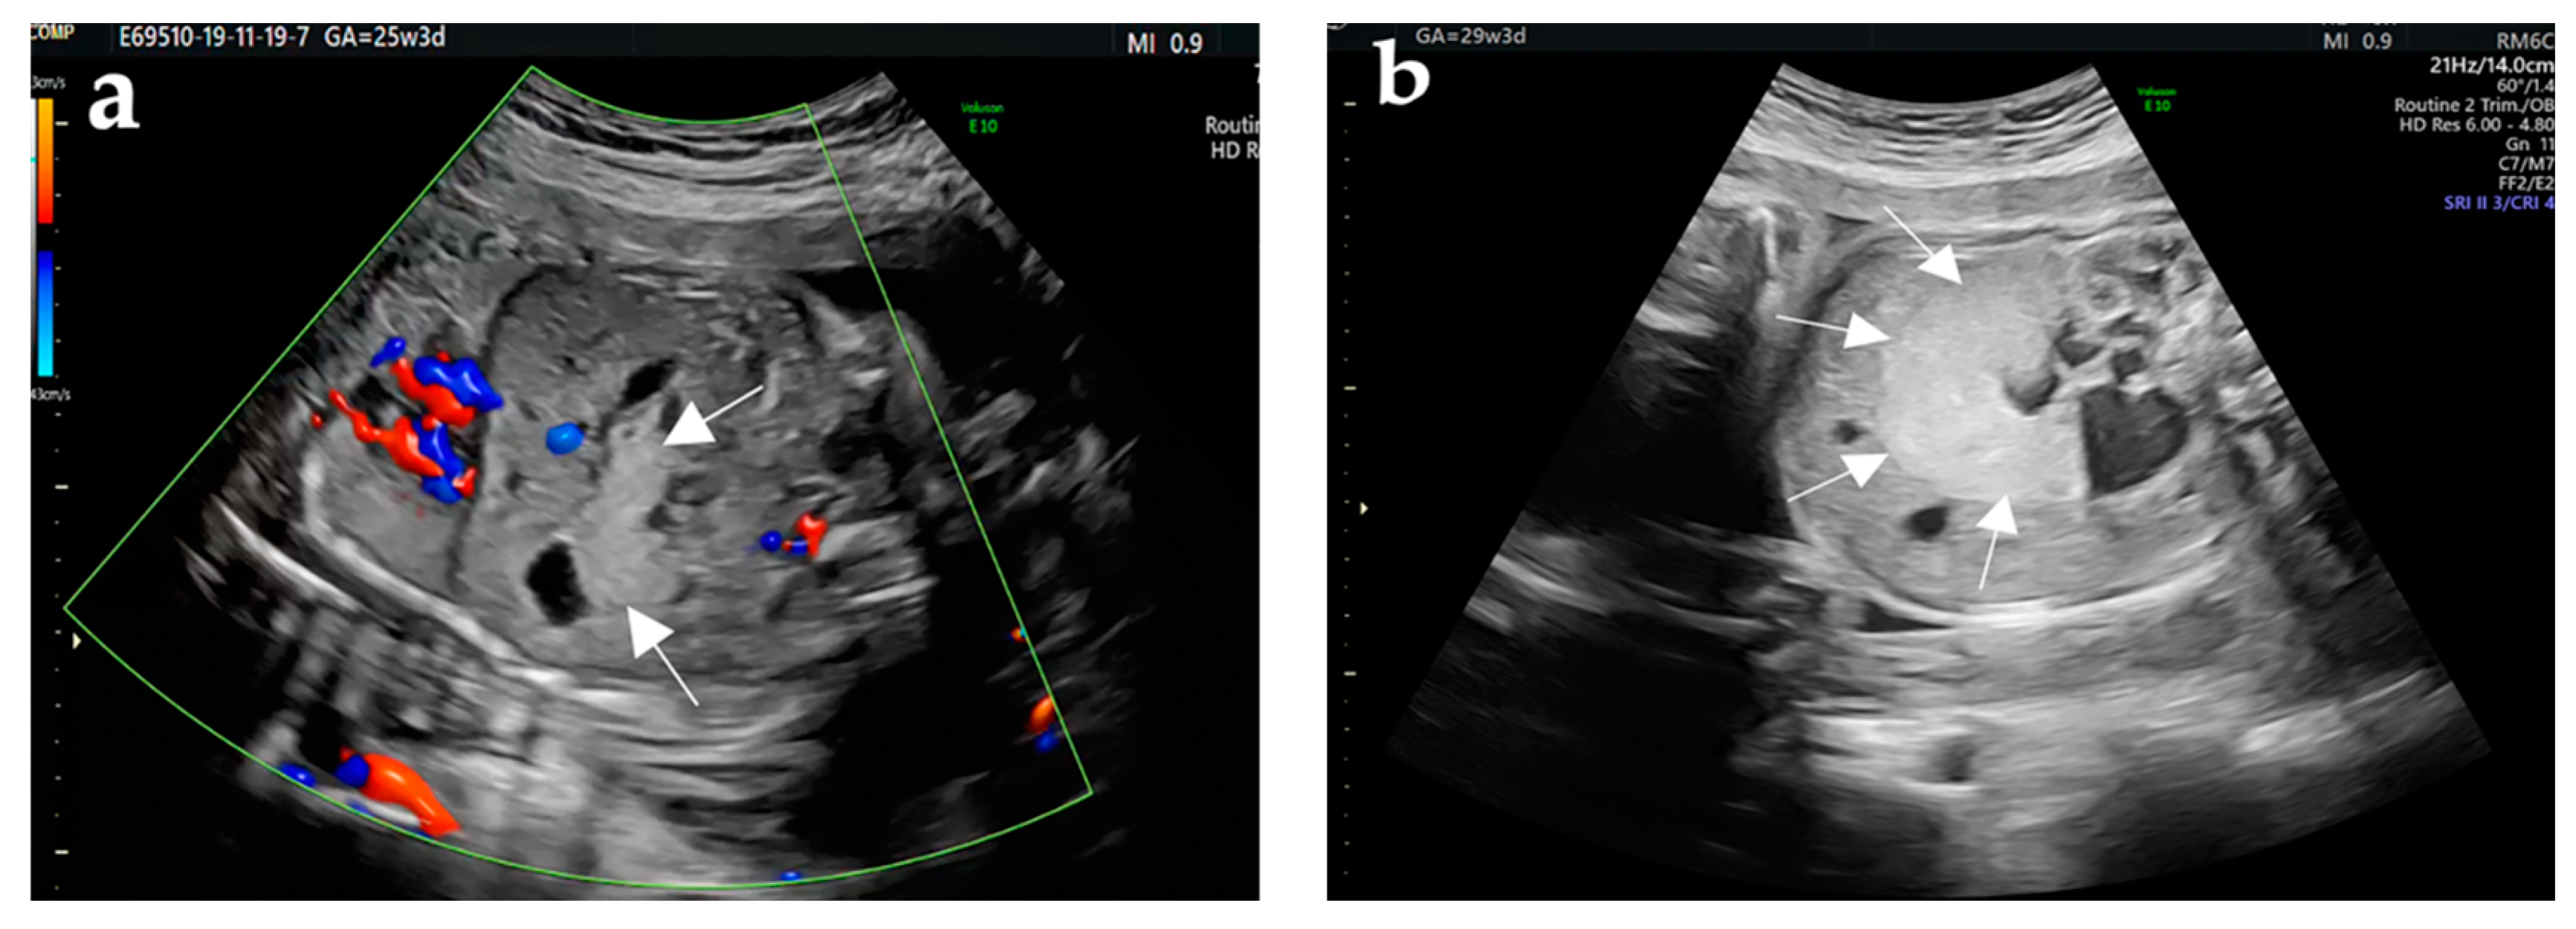

| Abdominal ultrasound | 25th week |

|

| Abdominal ultrasound | 29th week |